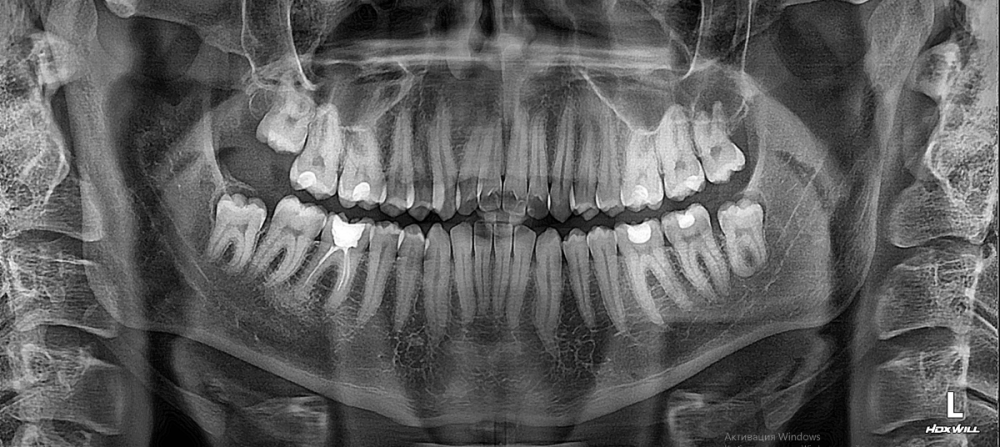

Dmitry002442 Опубликовано 21 июля, 2023 Поделиться Опубликовано 21 июля, 2023 (изменено) У ортодонта еще не был, хотел сначала тут поинтересоваться. Сделал снимки и получил следующее: сагиттальная щель 10,5 мм, параметр Wits 7,6 мм и прочее. Дистальный и открытый прикус. Хотел узнать необхо дима ли в таком случае члх или можно обойтись только брекетами? Изменено 21 июля, 2023 пользователем Dmitry002442 Ссылка на комментарий

АнтонТЛТ Опубликовано 21 июля, 2023 Поделиться Опубликовано 21 июля, 2023 Трг с расчетами и оптг это конечно хорошо, но нужны фото моделей челюстей или внутриротовые сканы. Думаю тут всё обойдется без члх, но возможно внутрикостные опоры нужны будут. 1 Ссылка на комментарий